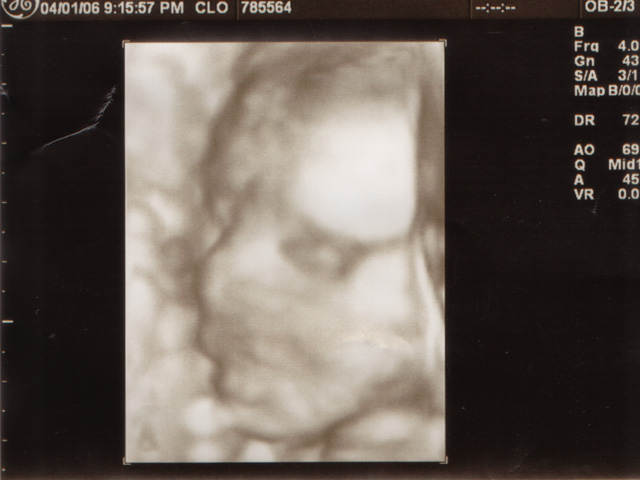

My sonograms.